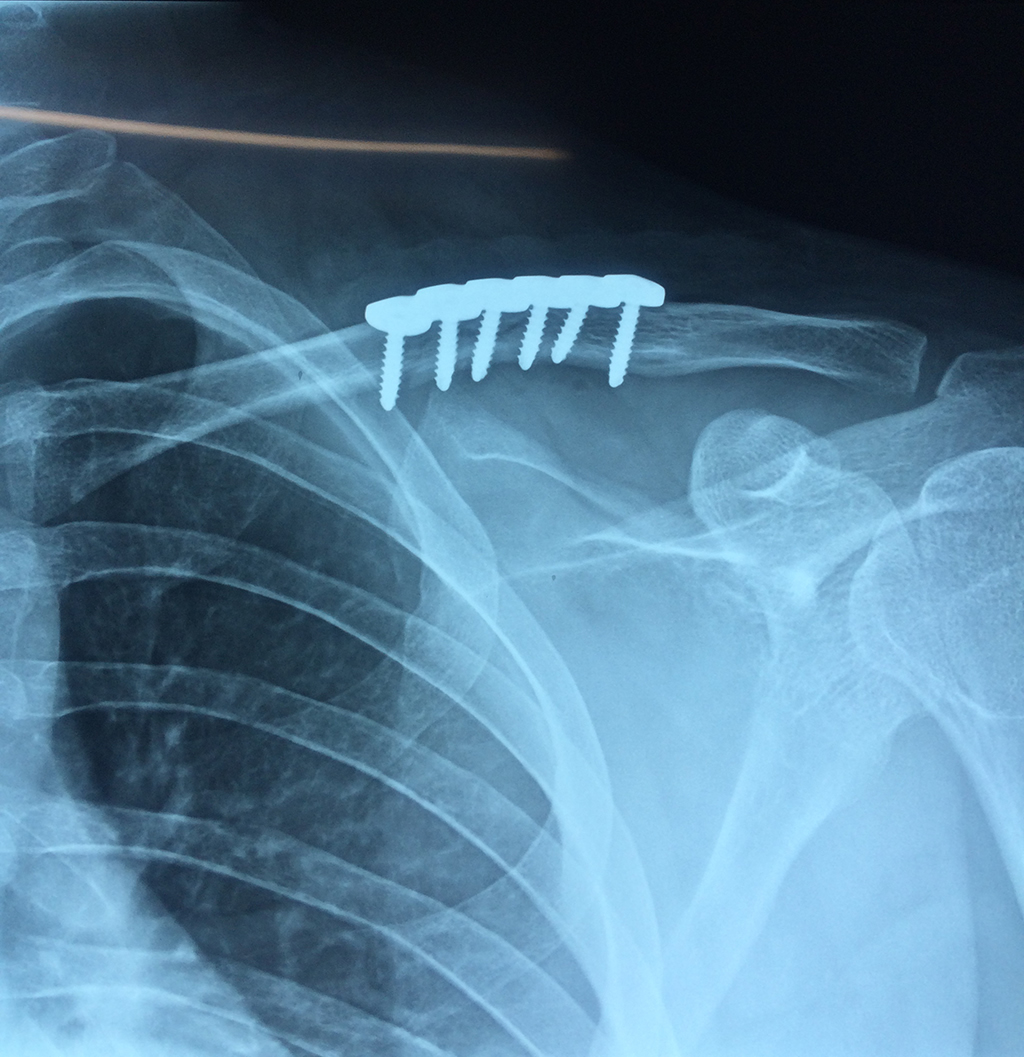

Cirugías de Húmero - Clavícula

La clavícula es un hueso largo, con forma de "S" itálica, situado en la parte anterosuperior del tórax. Junto con la escápula forman la cintura escapular. Se puede palpar por toda su longitud y se extiende del esternón al acromion de la escápula, siguiendo una dirección oblicua lateral y posterior.